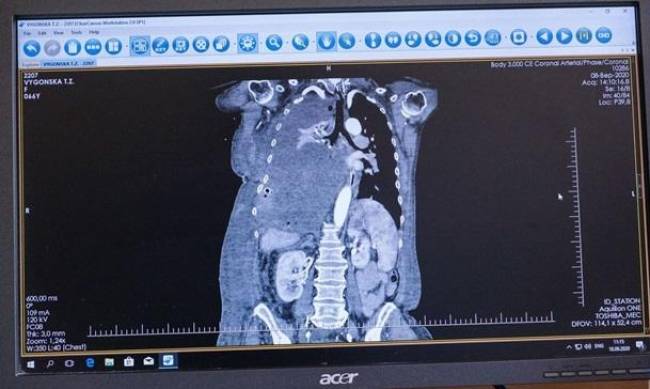

"66-летняя Татьяна Выгонская вместе с мужем живет в Хмельницкой области. Семья имеет восемь взрослых детей, один из сыновей - участник АТО. Женщина узнала об опухоли в легких три года назад, но из-за нехватки средств отказывалась от лечения. В мае Татьяна Выгонская почувствовала сильную одышку и слабость, поэтому была вынуждена обратиться за помощью по месту жительства, а оттуда ее отправили в Хмельницкую областную клиническую больницу, где провели обследование и приняли ряд анализов. Диагноз - солитарная фиброзная опухоль правого гемиторакса. Новообразование было таким большим, что срослось, зажало правое легкое и давило на левое легкое и сердце. Из-за размера опухоли женщину отказались оперировать, а местный онковрач посоветовал проконсультироваться у хирурга Виталия Соколова в Киеве", - говорится в сообщении.

В начале сентября в больнице Феофания провели сложную 12-часовую операцию с участием более 30 специалистов. Ее стоимость, с учетом использованной аппаратуры, препаратов и донорской крови, составляет около 1 млн грн.

При удалении опухоли использовался аппарат искусственного кровообращения (экстракорпоральной мембранной оксигенации легких (ЭКМО) - дорогое устройство, которое фактически выполняет функции легких и сердца.

"Таких операций в мире делается не очень много. У пациентки дважды останавливалось сердце. Один сет (набор для поддержания) для ЭКМО стоит 100 000 гривен, а стоимость аппарата - шести с половиной миллионов гривен. Успешные ЭКМО проводились в кардиохирургии, в частности детской. А применение у пациентки с опухолью в легких - впервые в Украине", - рассказал замглаврача Андрей Строкань.